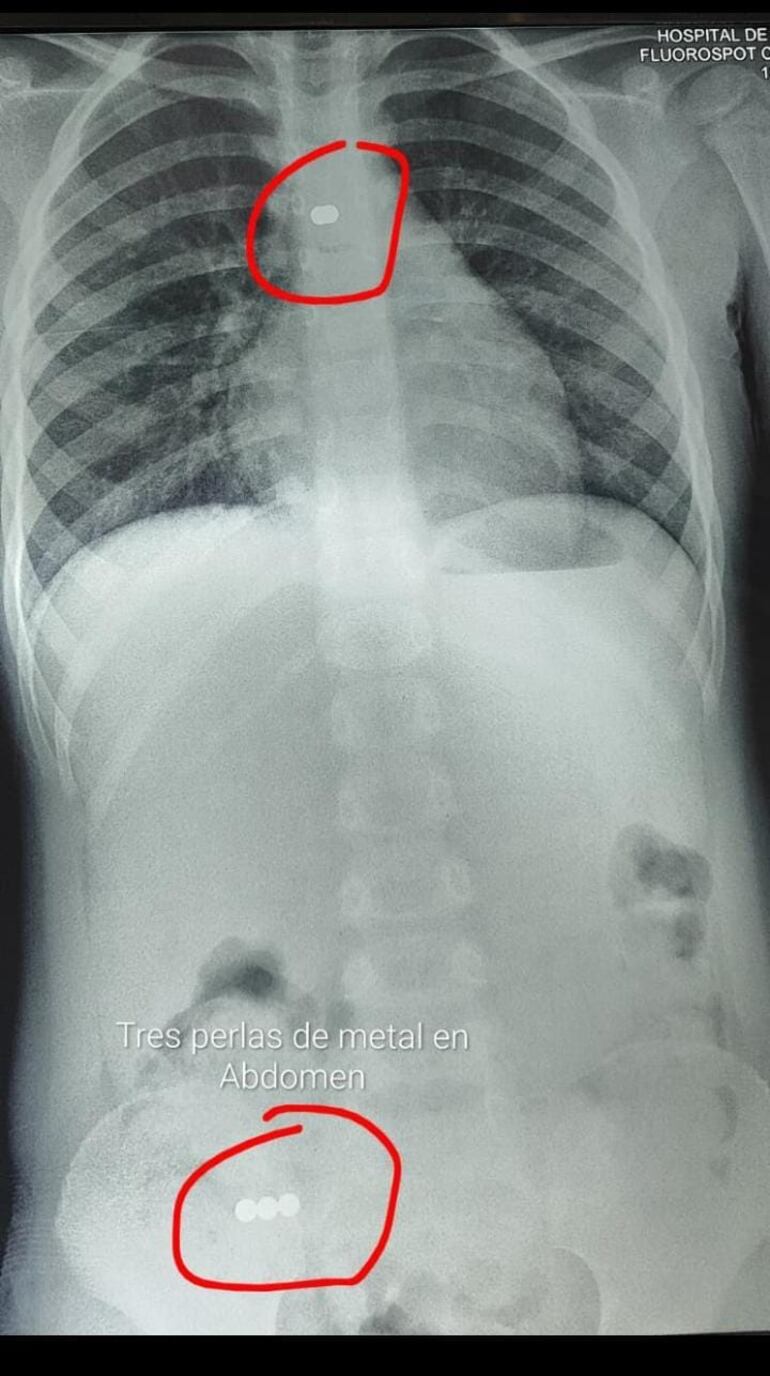

El collar se soltó y liberó las perlas, de las cuales cuatro fueron al aparato digestivo y una al pulmón, lo que causó una neumonía grave bilateral.

“Al ingresar observo pus en todos los bronquios y allá, en el fondo de la base del pulmón, la perla alojada”, relata.